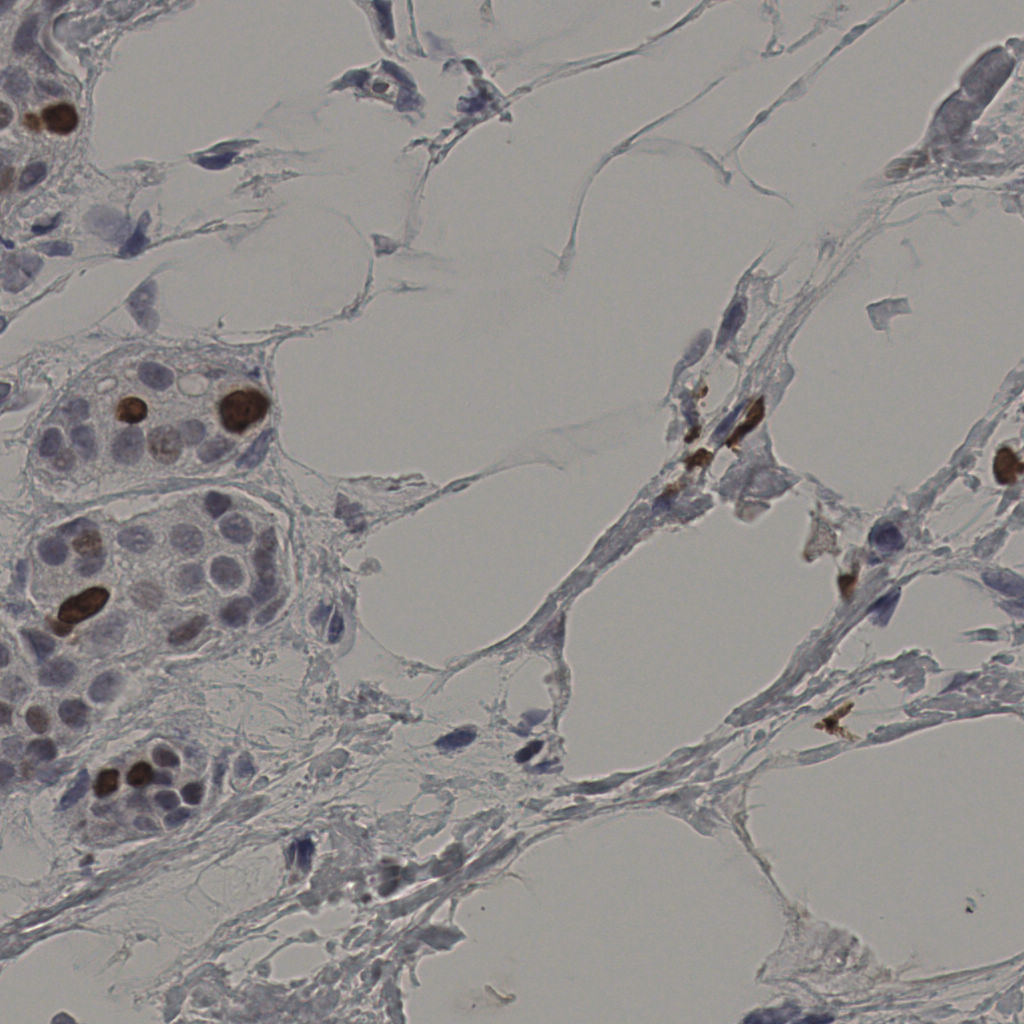

slice_37_9_x33152_y8064.png

slice_37_9_x33152...